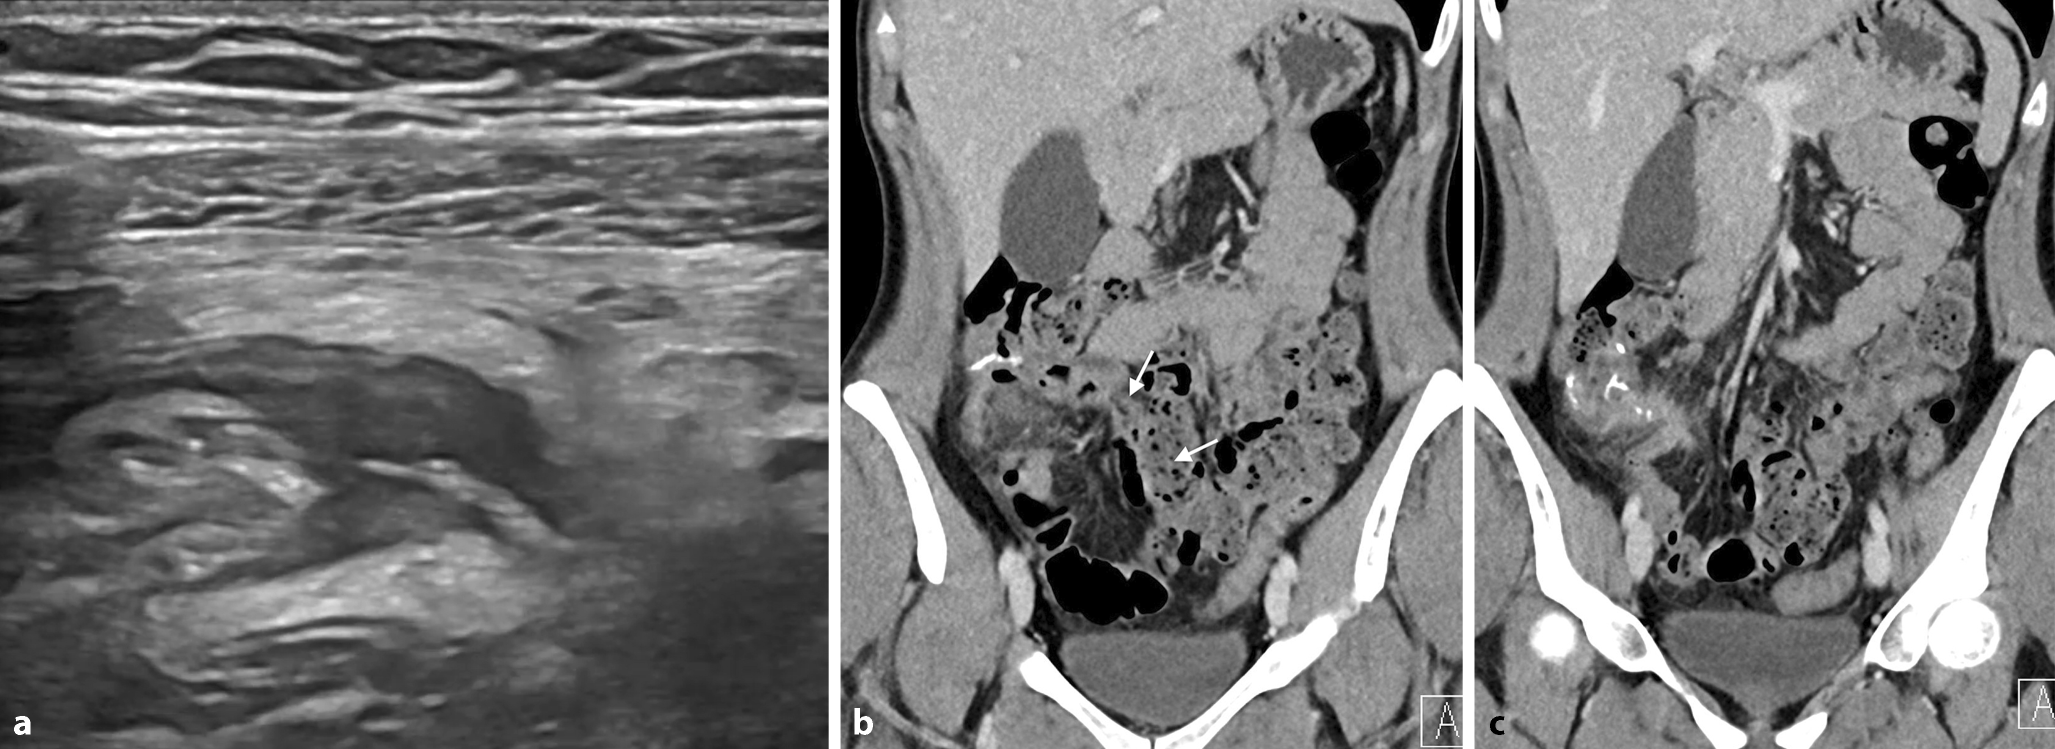

In Notfallsituationen wird häufig ein Mehrphasenprotokoll mit Akquisitionen in arterieller und portalvenöser Kontrastmittelphase eingesetzt, um vaskuläre Komplikationen, Blutungsquellen oder ischämische Veränderungen detektieren zu können. Bei Verdacht auf eine akute Blutung des Dünndarms kann eine zusätzliche native Phase zur Differenzierung von hyperdensem Darminhalt von intraluminalen Kontrastmittelfahnen hilfreich sein (Abb. 4). Die arterielle Phase ist dabei am sensitivsten für die Detektion einer aktiven Blutung [15].

Abb. 4

Patient mit postoperativem Hämoglobinabfall und Bauchschmerzen nach Dünndarmteilresektion: Die native Serie (a) zeigt Nahtmaterial im Anastomosenbereich. In der arteriellen Phase (b) ist ein Kontrastmittelextraluminat direkt neben der Anastomose erkennbar mit geringem Pooling in der venösen Phase (c), beweisend für das Vorliegen einer aktiven arteriellen Blutung

Die orale Verabreichung von Kontrastmittel ist derzeit Gegenstand kontroverser Diskussionen. In der Akutsituation ist sie oft nicht praktikabel oder diagnostisch nicht notwendig, wie beispielsweise bei Verdacht auf Darmobstruktion, zumal pathologisch distendierte prästenotische Darmschlingen bereits einen ausreichenden natürlichen Kontrast aufweisen (Abb. 5).

Abb. 5

Patient mit akuten Bauchschmerzen bei stattgehabter Appendektomie vor einigen Jahren: Die umgehend durchgeführte Computertomographie des Abdomens (a) zeigt distendierte Darmschlingen mit 2 Kalibersprüngen im Unterbauch (Pfeile) und nachfolgend kollabiertem Darm, wodurch sich der hochgradige Verdacht auf eine Inkarzeration einer Dünndarmschlinge durch eine Bride mit konsekutiver Dünndarmobstruktion ergab. b Intraoperativer Situs, der die Bride bestätigte. (Courtesy: Dr. C. Bichler, Medizin. Univ. Wien)